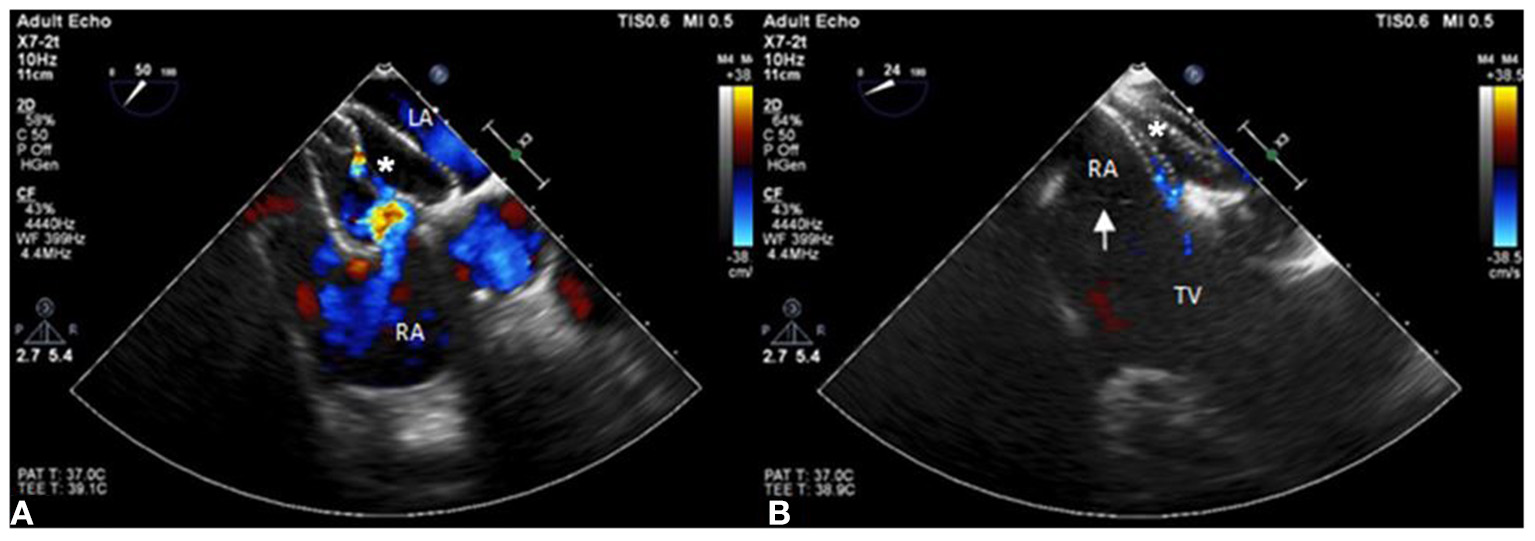

A 55-year-old female patient came to our hospital with a complaint of chest discomfort for 2 days. The electrocardiogram (ECG) revealed an incomplete right bundle branch (iRBBB) without ST segment elevation. Troponin-I, creatine kinase (CK), and creatine kinase-MB (CK-MB) levels were in the normal range. Chest X-ray revealed right ventricle hypertrophy (RVH) with prominent pulmonary congestion. Two secundum type ASDs with membranous remnants at the right atrium were noted in TTE. TEE was arranged for the membranous remnants at the right atrium and revealed double ASDs with iCTD at the connection of the right atrium and inferior vena cava (Figures 1A,B). Cardiac CT showed double ASDs, which were 21.2 and 13.6 mm in size, with iCTD (Figures 2A,B). During catheterization, no pulmonary hypertension was found, and the size of the larger ASD under balloon sizing was 29.2 mm. The ratio of pulmonary flow to systemic flow was 1.9:1. Therefore, a 30-mm Lifetech device was chosen to close these two ASDs. We chose a 7 French sheath to pass the larger ASD from the RA to LA and deploy the device to close the ASDs without detachment. However, transient heart ischemia with presence of ST segment elevation (Figure 3A) was noted and coronary sinus obstruction by the device was thought to be the cause. The shape of the device was also not feasible and many residual shunts were noted. Partial involvement of iCTD in the process of device deployment, which resulted in the obstruction of coronary sinus, was determined (Figure 4A). Hence, we withdrew the device immediately and the ST segment elevation recovered (Figure 3B).

Figure 4

The position of the ASD occluder. (A) The position of the ASD device is initially incorrect with part of the incomplete cor triatiatum dexter clamped and many residual shunts noted under TEE. (B) The position of the ASD occluder is good with a minimal residual shunt and the incomplete cor triatiatum dexter (arrow) is free from clamping by the device.

For the second attempt, a 7 French sheath passed the larger ASD using the same method as last time. The position of the device was adjusted more accurately than the first time to avoid iCTD involvement under TEE guidance. After deployment, the device was more stable than the first time, and no bradycardia or ST segment elevation were found on the electrocardiogram monitor. After device movement, we detached the device smoothly, and a minimal residual shunt without iCTD and tricuspid valve clamping was noted (Figure 4B). After the procedure, no complication was noted. Her chest tightness was improved and no residual shunt was noted in TTE during 6 months follow-up.